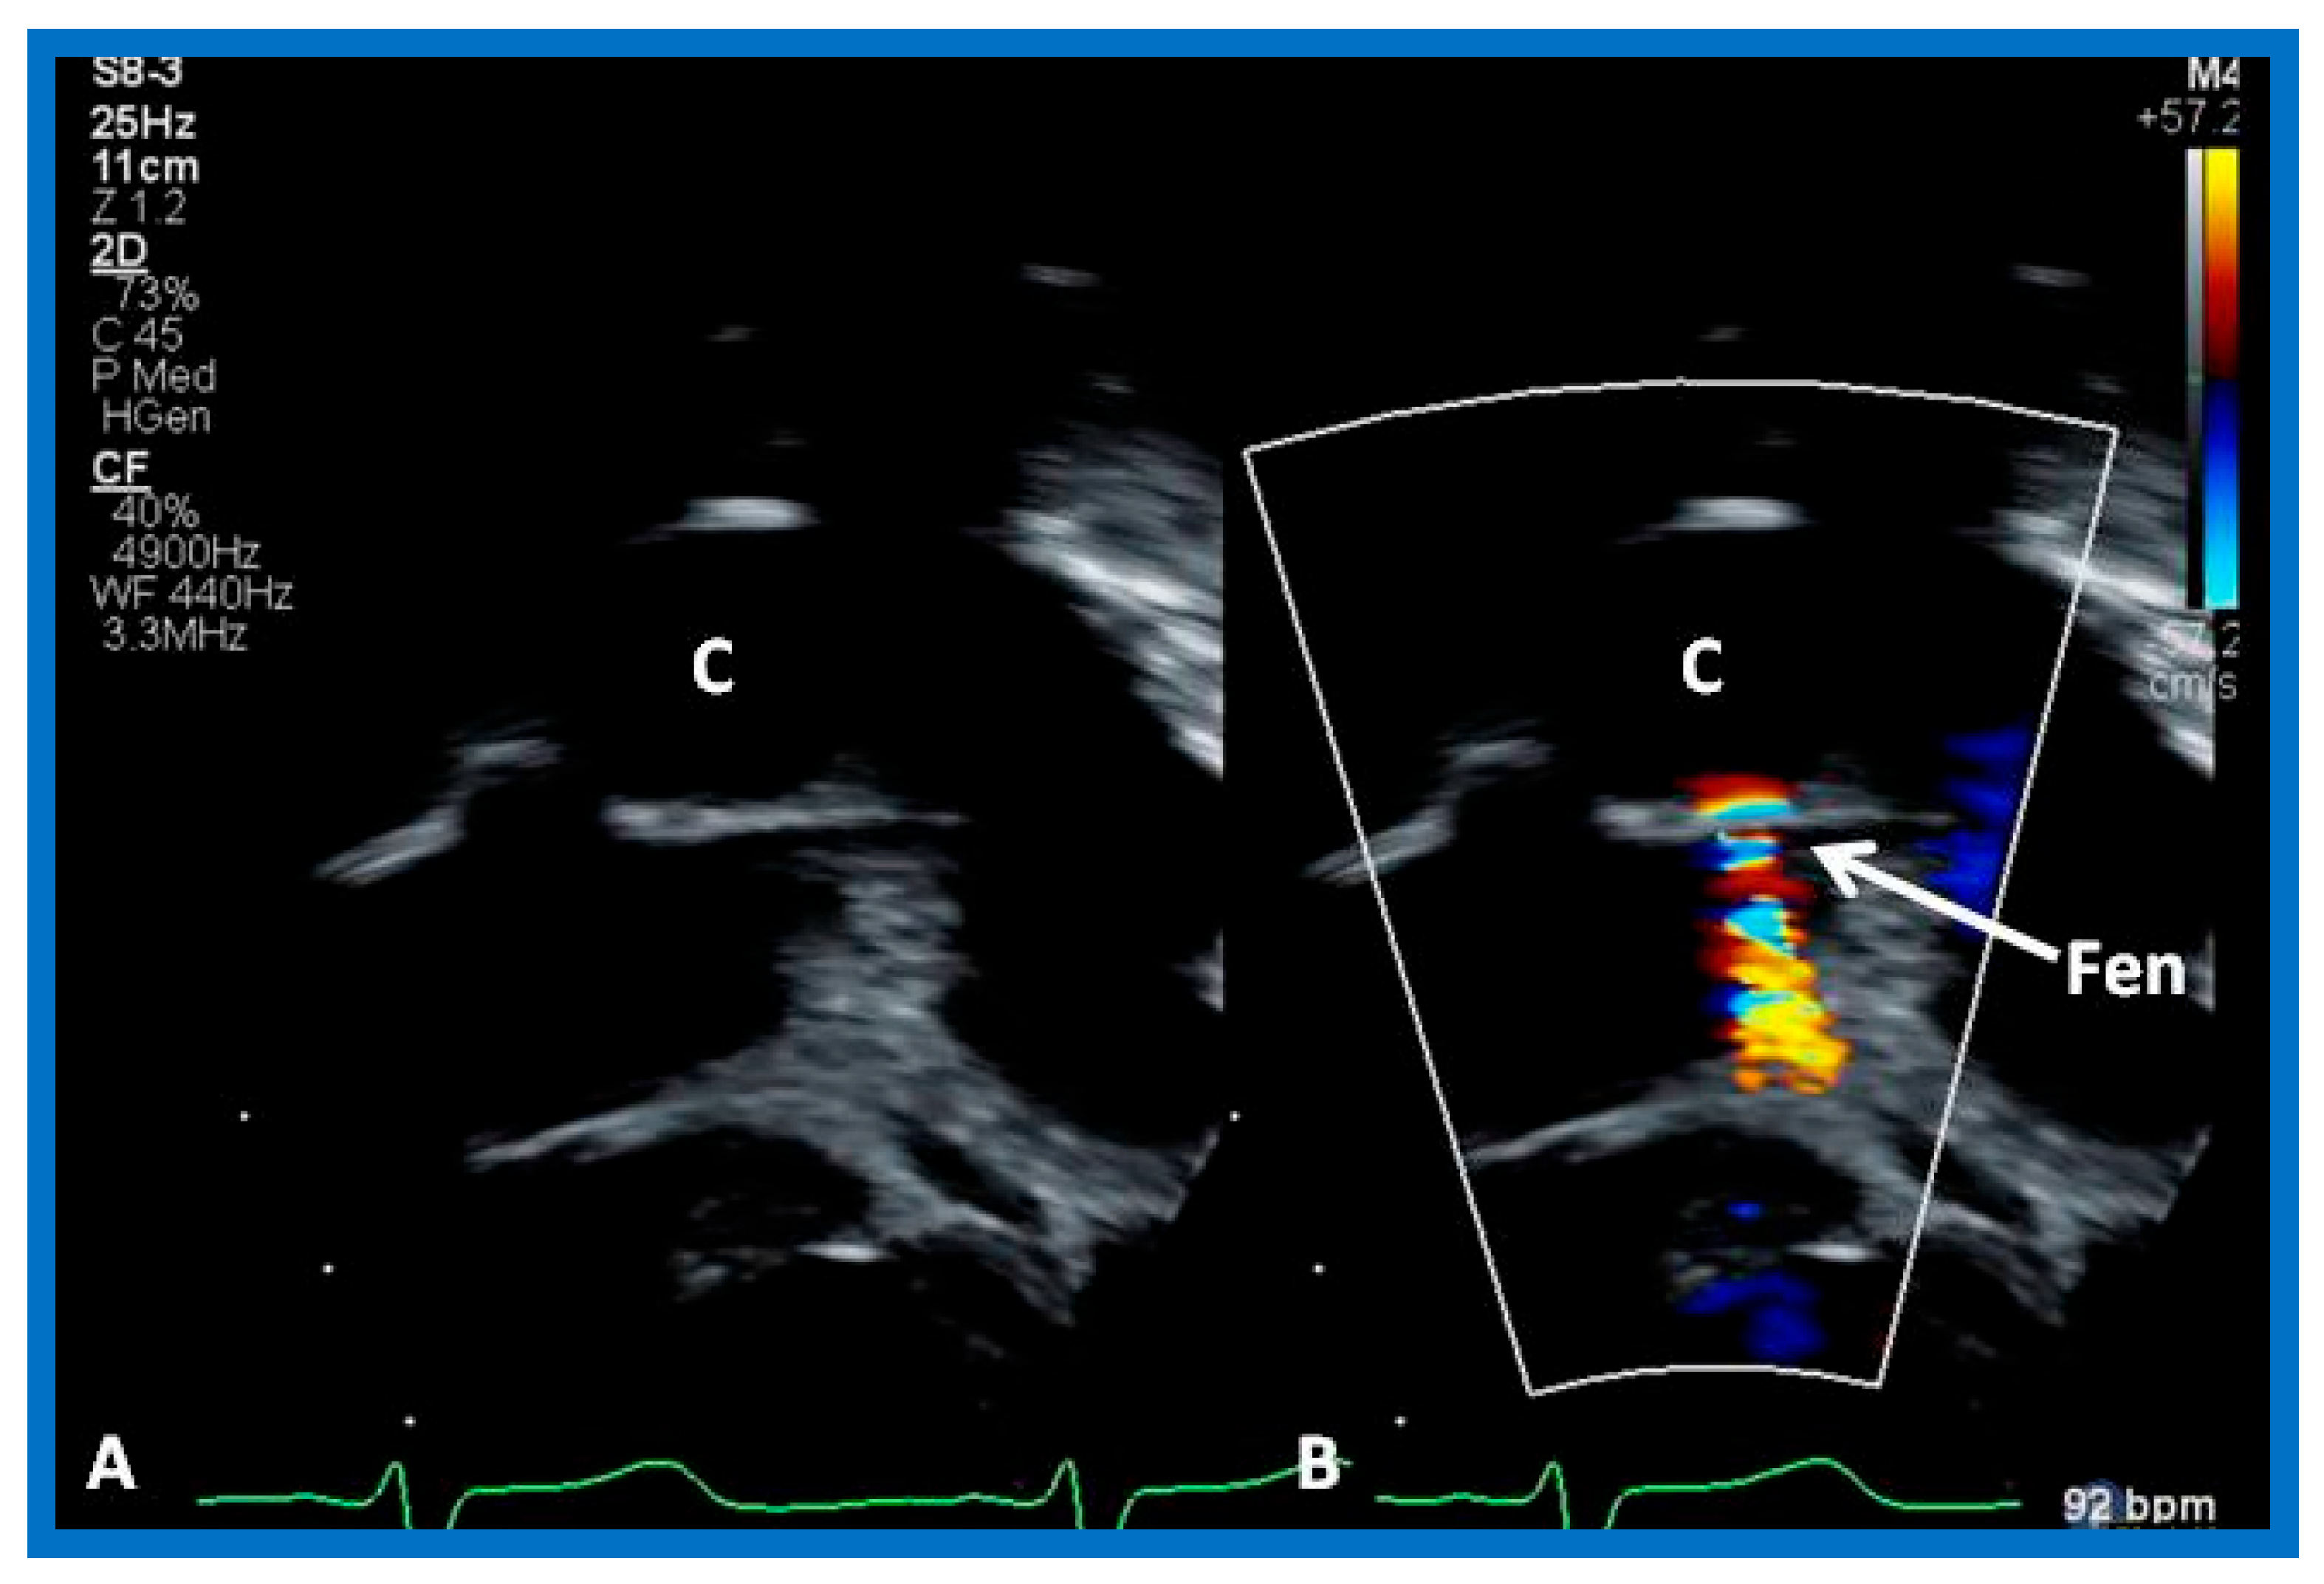

- Bridges, N.D.; Lock, J.E.; Castaneda, A.R. Baffle fenestration with subsequent transcatheter closure. Modification of the Fontan operation for patients at increased risk. Circulation 1990, 82, 1681–1689. [Google Scholar] [CrossRef]

- Laks, H.; Pearl, J.M.; Haas, G.S.; Drinkwater, D.C.; Milgalter, E.; Jarmakani, J.M.; Isabel-Jones, J.; George, B.L.; Williams, R.G. Partial Fontan: Advantages of an adjustable interatrial communication. Ann. Thorac. Surg. 1991, 52, 1084–1094; discussion 1094–1095. [Google Scholar] [CrossRef]

- Rao, P.S.; Chandar, J.S.; Sideris, E.B. Role of inverted buttoned device in transcatheter occlusion of atrial septal defects or patent foramen ovale with right-to-left shunting associated with previously operated complex congenital cardiac anomalies. Am. J. Cardiol. 1997, 80, 914–921. [Google Scholar] [CrossRef]

- Goff, D.A.; Blume, E.D.; Gauvreau, K.; Mayer, J.E.; Lock, J.E.; Jenkins, K.J. Clinical outcome of fenestrated Fontan patients after closure: The first 10 years. Circulation 2000, 102, 2094–2099. [Google Scholar] [CrossRef]

- Boudjemline, Y.; Bonnet, D.; Sidi, D.; Agnoletti, G. Closure of extracardiac Fontan fenestration by using the Amplatzer duct occluder. Arch. Mal. Du Coeur Vaiss. 2005, 98, 449–454. [Google Scholar]

- Rothman, A.; Evans, W.N.; Mayman, G.A. Percutaneous fenestration closure with problematic residual native atrial septum. Catheter. Cardiovasc. Interv. 2005, 66, 286–290. [Google Scholar] [CrossRef]